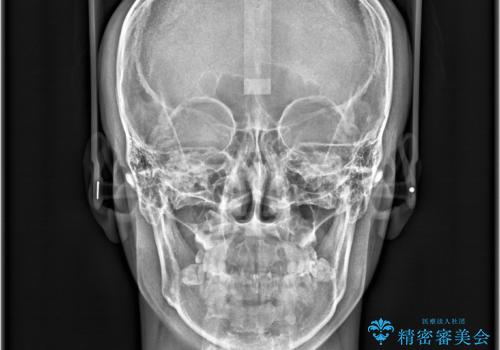

- 咬み合わせの不調和と歯並びのデコボコを主訴にご来院された患者様です。

精密矯正検査の結果、歯を抜かずに非抜歯でワイヤー矯正で治療を行う方針としました。

叢生(歯のデコボコ)の量が多く、加えてディープバイト(過蓋咬合)や重度の捻転も認められたため、リンガルアーチやマイクロインプラントなどの補助装置を併用し、治療を進めました。

治療途中では咬み合わせの改善を目的としてバイトアップを行い、歯の捻転や叢生を改善しつつ、機能的に安定した咬合を獲得しています。

治療期間は3年2ヵ月と比較的長期となりましたが、見た目の歯並びだけでなく、咬み合わせまでしっかり整えた症例です。